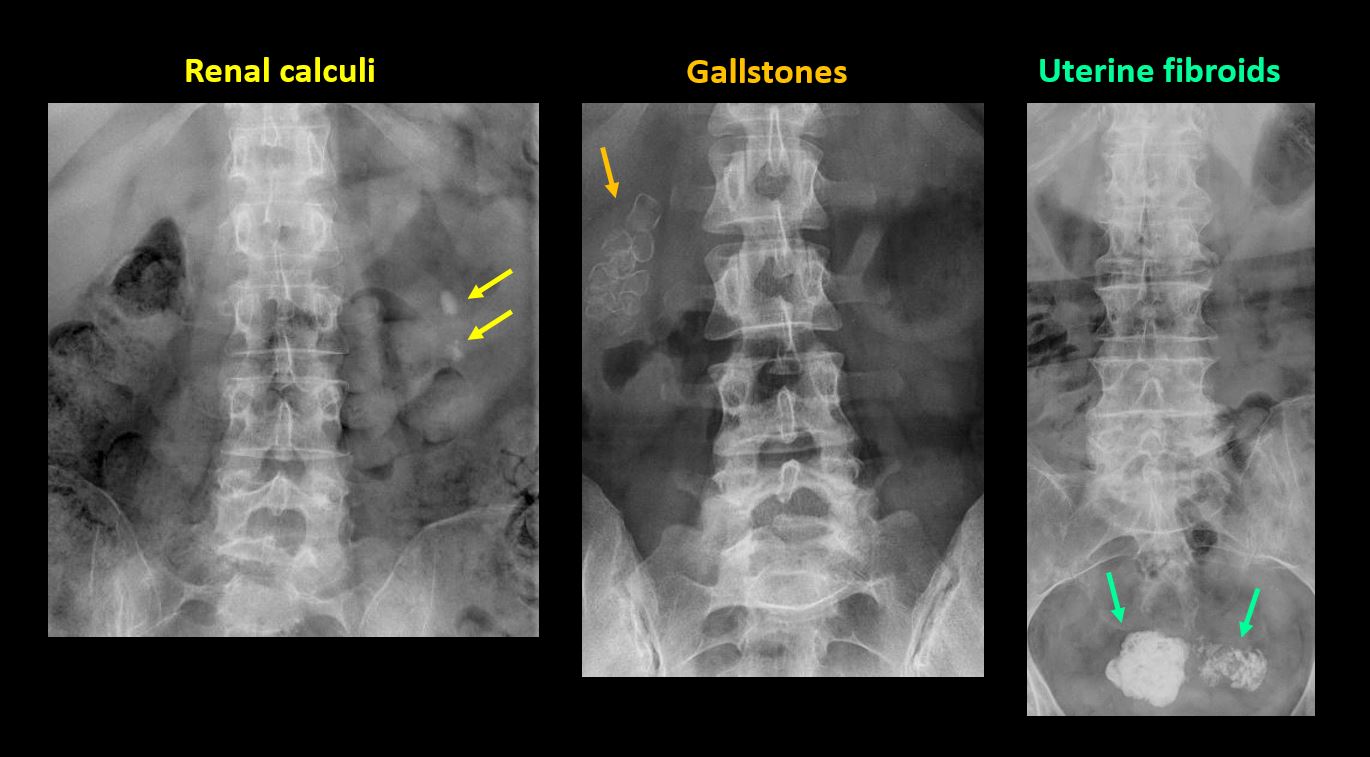

Section 1 Submit Findings CB1239 Findings Technique The thoracolumbar junction and/or the lumbosacral junction is/are not entirely included on the exam. Yes No The exam is over or under penetrated. Yes No The exam is limited by overlying structures, bones or soft tissues, patient positioning, support devices, or motion. Yes No Prevertebral and paravertebral soft tissues The prevertebral or paravertebral soft tissues are abnormal. Yes No Spinal alignment The vertebral bodies are abnormally aligned. Yes No The anterior and posterior vertebral body lines are abnormal or interrupted. Yes No The visualized spinous processes are malaligned or distracted on the AP and/or lateral view(s). Yes No There is reversal or straightening of the normal lordosis or scoliosis of the lumbar spine. Yes No Vertebral bodies, posterior elements and included sacral segments There are more or less than the expected 5 non rib-bearing vertebral bodies. Yes No There is a transitional motion segment at the lumbosacral junction (sacralization of L5 or lumbarization of S1). Yes No There is a fracture or distraction of a vertebral body, transverse or spinous process, or other posterior element. Yes No There is anterior wedging and/or compression of a vertebral body or end plate. Yes No There is an end plate avulsion or other fracture. Yes No There is displacement of a fracture fragment into the soft tissues or spinal canal. Yes No There is lucency or defect of the pars interarticularis from spondylolysis. Yes No There is an abnormality of a pedicle or lamina on the frontal or lateral view. Yes No There is a fracture, erosion, sclerosis, lytic, or blastic lesion of a pedicle or lamina. Yes No There is evidence of a lytic or sclerotic lesion, or disruption of the trabecular pattern of a vertebral body, end plate, or sacrum. Yes No There is a fracture or interruption of the arcuate lines of the sacrum. Yes No There is erosion, sclerosis, narrowing, or other abnormality of a sacral foramen or the SI joints. Yes No There is focal or diffuse abnormal mineralization of the lumbosacral spine. Yes No Disc spaces and facet joints There is distraction or focal widening of a disc space. Yes No There is disc space narrowing with or without erosive or sclerotic changes of the end plates or subchondral bone other than from degenerative change. Yes No There is anterior or posterior spondylolisthesis, subluxation, or rotational abnormality at a disc space. Yes No There is widening, rotational abnormality, or displacement of facets at any motion segment. Yes No There is facet joint narrowing or sclerosis other than from degenerative change. Yes No There is narrowing or encroachment of a neural foramen other than from degenerative change. Yes No There are degenerative changes present that might explain the patient’s symptoms. Yes No Additional soft tissues and bones (lower thorax, abdomen, and pelvis) There is abnormal bowel or bowel gas pattern. Yes No There are gallstones, vascular, renal, pelvic, or other soft tissue calcifications present. Yes No There is free intraperitoneal or retroperitoneal air or other abnormal air in the included chest, abdomen, or pelvis. Yes No The included thoracic spine, ribs, and remainder of the bony pelvis are abnormal. Yes No There is abnormality of the lower chest and/or diaphragm. Yes No There is a foreign body or there are post surgical changes of the bones or soft tissues of the included lower thorax, abdomen, and pelvis. Yes No There is an abnormality or complication of post surgical hardware/device. Yes No N/A There are support lines or tubes in an abnormal position. Yes No Other findings There are other existing conditions that might be contributing to symptoms which can or should be further evaluated non-emergently. Yes No